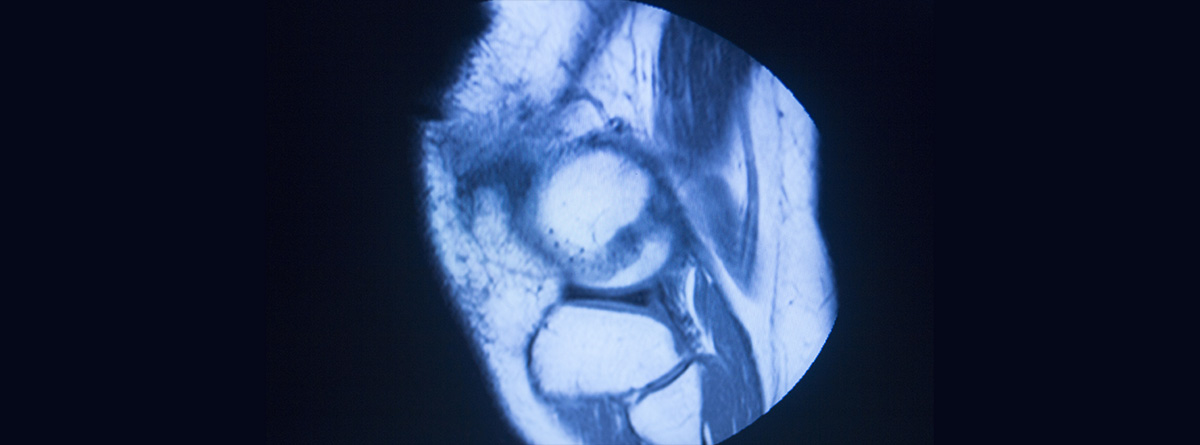

El diagnostico se basa principalmente en la historia clínica y una buena exploración física, donde se provocará dolor al presionar a lo largo del borde interno de la tibia. En algunos casos de sospecha o posibilidad de otro diagnóstico, se pueden usar técnicas de imagen como radiografías para descartar fractura por estrés o sobrecarga ósea, ecografías y solo rara vez se precisa de técnicas más sofisticada como resonancia magnética (RM).